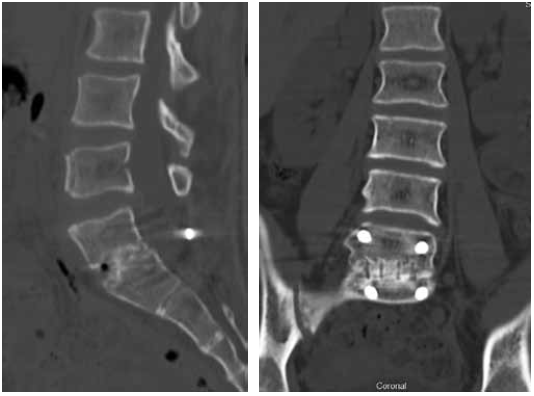

Considering the persistent pain syndrome after the conservative treatment and progressive nature of spondylolisthesis of L5, the following surgical intervention was performed: L5 laminectomy, microsurgical decompression of the spinal cord roots, complete reduction of the L5 vertebra, transpedicular fixation of the L5–S1 with additional fixation in the pelvic bone, and posterior interbody fusion of L5–S1. The duration of the surgery was 355 mins; the volume of blood lost was 800 ml. The patient was activated on the day 2 after surgery. During the postoperative period, the radicular pain syndrome had regressed completely, and no neurological disorders were detected. According to the control radiography, the restoration of the anatomical relationship of the vertebrae was noted. The position of the screws and implants was correct (Fig. 2). During the follow-up period, the patient had no complaints. After 1.5 years, MSCT revealed the formation of a reliable artifactual block, and the integrity of the surgical hardware was preserved (Fig. 3).

Fig. 2. Radiography of the lumbar spine in two views immediately after the surgery